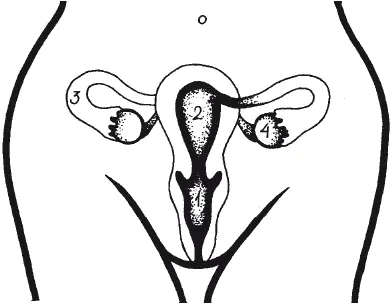

К внутренним органам относятся влагалище, матка, маточные трубы и яичники (рис. 1).

Рис. 1. Внутренние женские половые органы: 1 — влагалище; 2 — матка; 3 — маточная труба (яйцевод); 4 — яичник

Влагалище (vagina) представляет собой мышечную, эластичную трубку длиной 8–9 см. Нижний конец ее расположен под девственной плевой, а верхним концом она охватывает шейку матки. Стенки влагалища состоят из нескольких мышечных слоев, способных к растяжению и сокращению.

Матка — полый мышечный орган — состоит из тела матки и шейки. У новорожденной девочки матка имеет массу около 2 г, длина органа 2,5–3,5 см. Уже к 10–12 годам вес матки удваивается, размер увеличивается до 5,5 см (около 3,5 см приходится на долю тела матки и примерно 2,5 см — на шейку), а к 15 годам масса матки — 6,6 г, длина — около 7 см (рост происходит за счет увеличения тела органа). В период половой зрелости вес матки достигает 50 г.

Состоит орган из трех слоев. Изнутри полость выстлана слизистой оболочкой (с началом периода полового созревания в ней происходят циклические изменения, и ежемесячно она отторгается в виде кровянистых выделений, или менструации), затем идут мышечная ткань (структура ее очень сложна) и поверхность, обращенная в брюшную полость и покрытая так называемой серозной оболочкой.